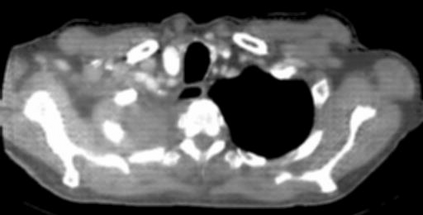

Due to the constraints of the imaging device and high cost in operation time, computer tomography (CT) scans are usually acquired with low intra-slice resolution. Improving the intra-slice resolution is beneficial to the disease diagnosis for both human experts and computer-aided systems. To this end, this paper builds a novel medical slice synthesis to increase the between-slice resolution. Considering that the ground-truth intermediate medical slices are always absent in clinical practice, we introduce the incremental cross-view mutual distillation strategy to accomplish this task in the self-supervised learning manner. Specifically, we model this problem from three different views: slice-wise interpolation from axial view and pixel-wise interpolation from coronal and sagittal views. Under this circumstance, the models learned from different views can distill valuable knowledge to guide the learning processes of each other. We can repeat this process to make the models synthesize intermediate slice data with increasing inter-slice resolution. To demonstrate the effectiveness of the proposed approach, we conduct comprehensive experiments on a large-scale CT dataset. Quantitative and qualitative comparison results show that our method outperforms state-of-the-art algorithms by clear margins.